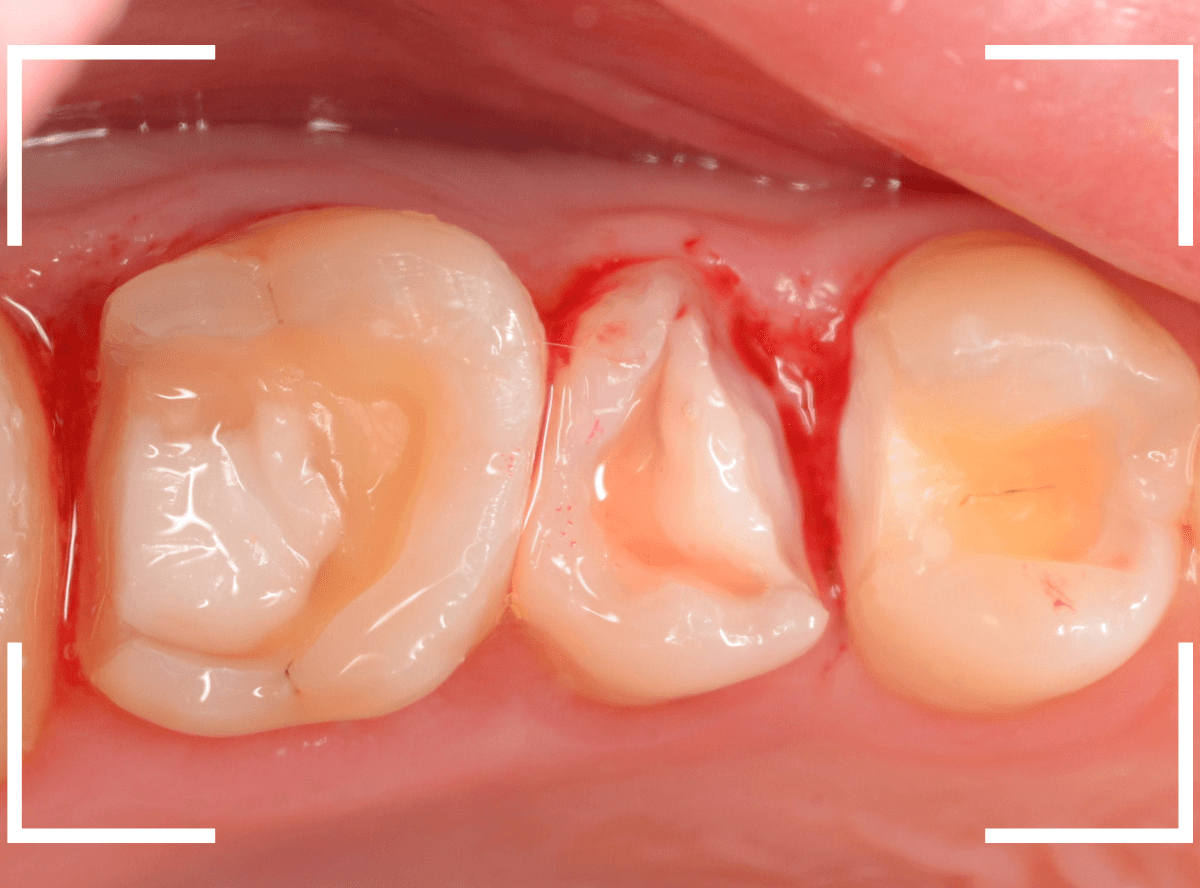

Case.28 虫歯治療後、半年以上来院されなかった患者さん

虫歯を治療して、セメントで歯を削った部分を封鎖した後、再修復を検討中で、半年以上来院されなかった患者さんです。

虫歯を治療して、セメントで封鎖した状態というのは、家でいえば、しっかりした屋根がない状態です。

今回は、セメントの一部がはがれる程度で済んでいましたが、虫歯が再発し、再治療、最終修復物の変更の可能性も出てきます。

皆さんも治療は中断せずに最後まで通院するようにしてくださいね。

治療再開後、セラミックの最終修復を希望されましたので、歯をトリミングし、型取りします。

模型上で精密に製作します。